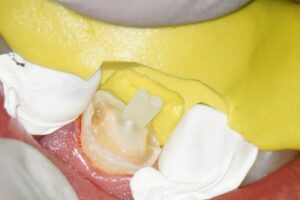

Das Zahnfragment hatte eine gute Passung auf den frakturierten Stumpf. So konnte im Vorfeld ein Silikonabdruck als Vorwall für den Kompositaufbau erstellt werden. Die endodontische Therapie sowie der Füllungsaufbau erfolgten ausschließlich unter dem hochauflösenden OP-Mikroskop (Zumax OMS2350). Die zu behandelnde Region wurde mit Ubistesin 1/200000 lokal betäubt. Anschließend wurde von 11 bis 22 ein Kofferdam angebracht. Der Zahn wurde mit einem konischen Diamanten trepaniert, die Trepanationsöffnung mit Gates-Glidden-Bohrern erweitert. Die Aufbereitung erfolgte mit dem Reciproc Blue System bis zur Größe 50.05.

Guttapercha und AH Plus als Sealer. Anschließend wurden aufgrund der ovalen Kavität zwei Glasfaserstifte zur Stabilisation der Füllung eingebracht und mit Luxacore adhäsiv verklebt.

Der provisorische Aufbau erfolgte durch den Endodontologen mit vorab gefertigtem Silikonschlüssel mittels Tetric Flow und Ceram A3,5 als Abschluss der Single-Visit-Behandlung. Die endgültige Krone konnte am 12. Juni 2025 eingegliedert werden.